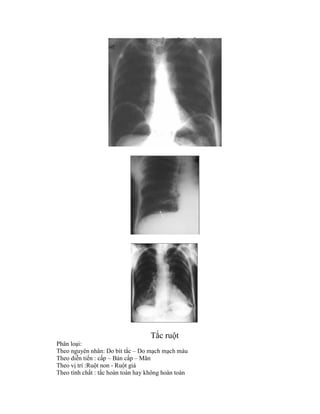

Phân loại:

Theo nguyên nhân: Do bít tắc – Do mạch mạch máu

Theo diễn tiến : cấp – Bán cấp – Mãn

Theo vị trí :Ruột non - Ruột giá

Theo tính chất : tắc hoàn toàn hay không hoàn toàn

Phân biệt : tắc cơ năng # tắc cơ học

Tắc ruột Phân loại: Theonguyên nhân: Do bít tắc – Do mạch mạch máu Theo diễn tiến : cấp – Bán cấp – Mãn Theo vị trí :Ruột non - Ruột giá Theo tính chất : tắc hoàn toàn hay không hoàn toàn

Phân biệt :tắc cơ năng # tắc cơ học A / Tắc ruột non Nguyên nhân : Dày dính Do u Do thoát vị Hình ảnh : b/ Tắc ruột già ( Colonic obstruction ) : ít gặp hơn ruột non khoảng 5 lần Khoảng 20-25% ở Zichma so tắc nói chung , diễn tiến chậm Nguyên nhân : U tân sinh ( Lành hay ác ) Co thắt ( Do túi thừa hay thiếu máu ) Thoát vị nghẹt ( Incarcerated hernia ) Xoắn ruột ( Volvulus ) Táo bón ( Obstipation ) Hình ảnh : Chung - Tắc zichma do u : Bơm baryet c/ Hình ảnh phân biệt : Vị trí hơi :

Chú ý :Bình thường có khoảng # 3 đám hơi : Hơi dạ dày – Hơi gối trên hành tá tràng và góc đại tràng Số lượng quai ruột Hình dạng quai ruột Thành quai ruột Đường kính ngang và dọc của quai ruột Nếp niêm mạc ruột non Đại tràng Khẩu kính quai ruột Hẹp : 3-5 cm > 5 cm Đừơng kính chân quai Rộng > cao Cao > rộng Số lượng quai Nhiều ít Vị trí quai Trung tâm Ngoại vi Nếp niêm mạc Nhiều ít